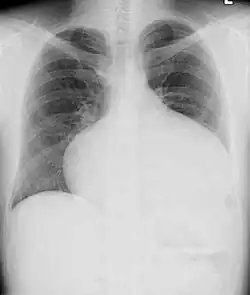

Adults with an uncorrected ASD present with symptoms of dyspnea on exertion (shortness of breath with minimal exercise), congestive heart failure, or cerebrovascular accident (stroke). They may be noted on routine testing to have an abnormal chest X-ray or an abnormal ECG and may have atrial fibrillation. If the ASD causes a left-to-right shunt, the pulmonary vasculature in both lungs may appear dilated on chest X-ray, due to the increase in pulmonary blood flow.[36]

ASD with pulmonary embolism resulting in a right-to-left shunting of blood[39]